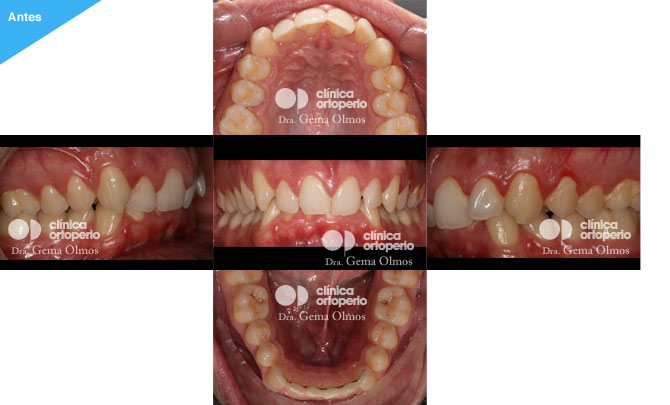

Caso 6. Clase II/ 2 subdivisión con apiñamiento.

En este caso los problemas a resolver eran el mal encaje de las piezas en la lado derecho, el apiñamiento, y un sobremordida excesiva (los dientes superiores cubrían por completo a los inferiores, limitando la libertad de movimientos de la mandíbula).

El tratamiento se realizó con brackets linguales (Incognito) y la extracción de un premolar superior.